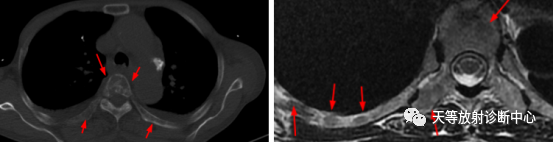

▲多发性骨髓瘤,椎体及多发肋骨穿凿性骨质破坏,范围广泛。